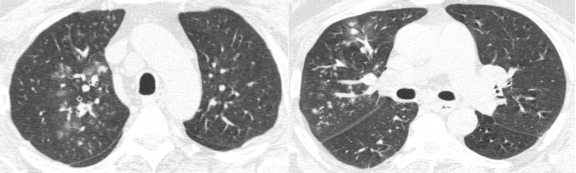

这是另外一个例子,双肺有斑片状的磨玻璃影,同时看到了有少量囊腔,还看到了正常密度的肺脏,双下肺靠近胸膜的地方有少量实变。

ero为什么不显示叶俏教授:HRCT是发现和鉴别「过敏性肺炎」的重要环节,何种表现指向预后不良?使患者发病的危害因素躲在哪些环境中?_https://www.jmylbn.com_新闻资讯_第23张